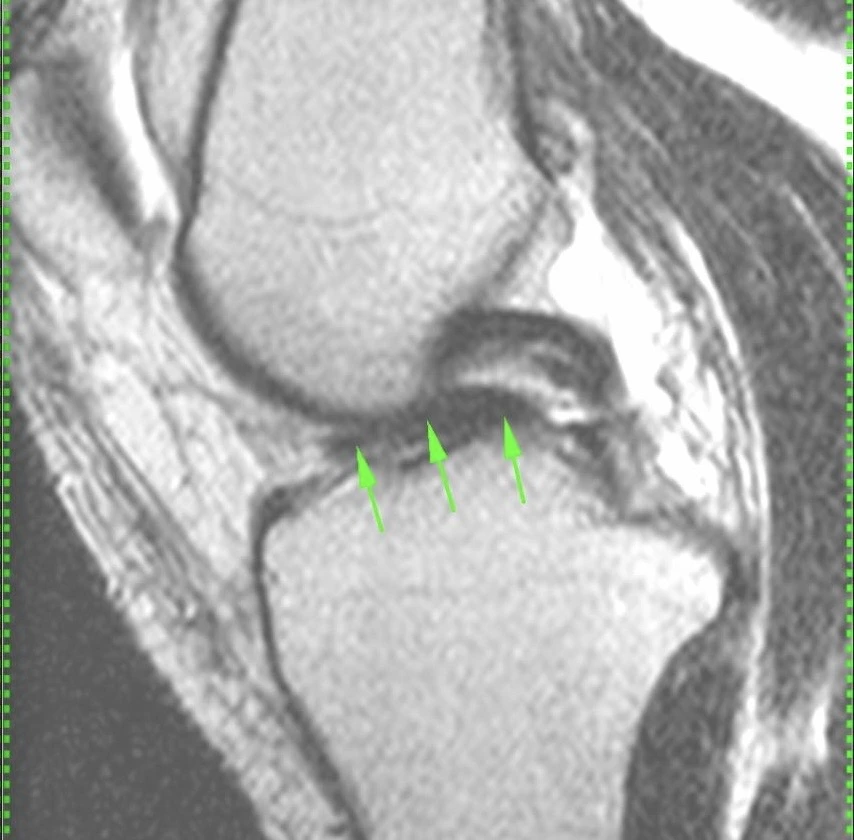

Обширная, ветвистая венозная мальформация (ранее известная, да и до сих пор тоже, как гемангиома) мягких тканей области коленного сустава.

Картина типичная, дифференциальная диагностика не требуется.

Представляет собой скопление аномальных, расширенных, извитых венозных сосудов, стенка которых гистологически не отличается от стенок обычных вен. Хорошо видны связи мальформации с обычными венами. Внутри некоторых из полостей видны выпадение сигнала, которые являются флеболитами (кальцинированными внутрисосудистыми тромбами).

Кстати, может никак не проявляться клинически, будучи даже таких больших размеров.